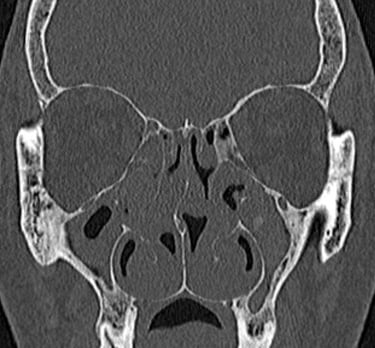

CT (kompjuterizirana tomografija)

U slučajevima kada su potrebne dodatne informacije, CT nosa i sinusa pruža trodimenzionalni prikaz unutrašnjih struktura. Pomaže u otkrivanju:

Precizne lokacije devijacije septuma.

Prisutnosti polipa, cista ili upalnih promjena.